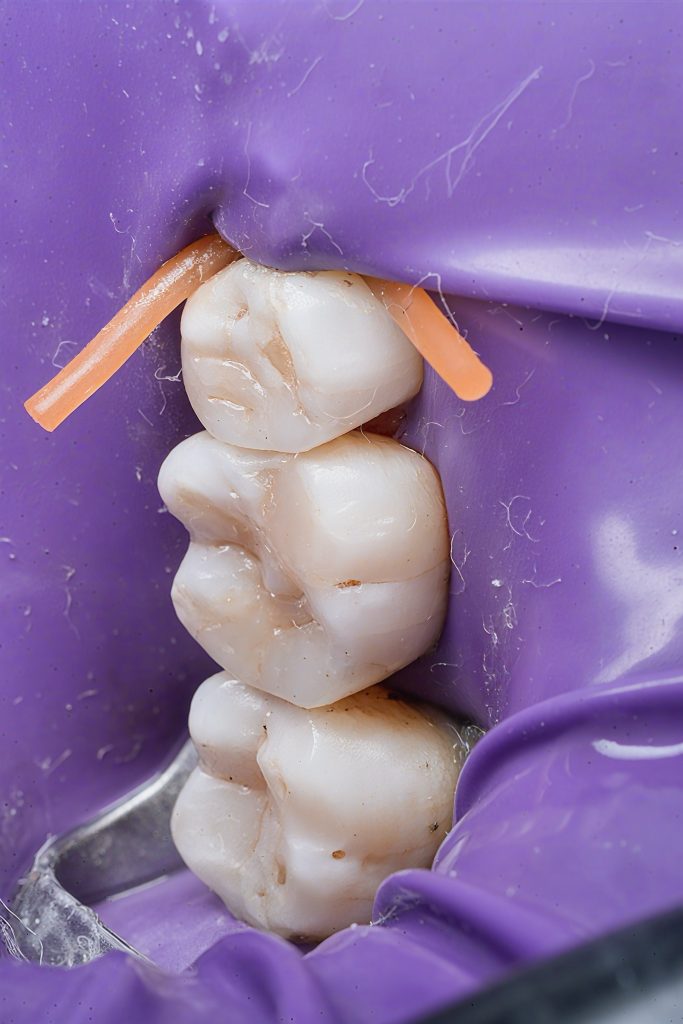

Clinical Pictures (Isolation & Access)

Image 3:

“Initial clinical presentation showing occlusal fissure staining, marginal breakdown and early proximal cavitation.”

Image 4:

“Rubber dam isolation achieved using sectional clamp. Cavities visible under magnification.”

Image 5–6:

“Sectional matrices placed with wooden wedges for controlled separation and optimal gingival adaptation.”